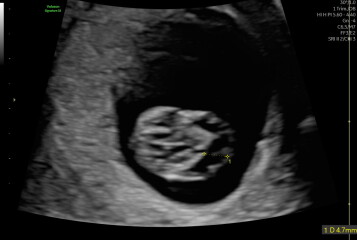

I went for what was meant to be a reassurance scan today at 10+2 weeks scan (I’ve had a scan at 6,8, 9 due to previous miscarriages and minor bleeding). What I was hoping would be a fun experience for my partner and I turned into us leaving sick with worry. The sonographer said the NT was thickened and there was a very large amount of fluid around the fetus’s head (4.7mm).

I’m preparing for the worst at my 12 week scan and test. I just wondered if anyone has had this level of fluid at 10weeks and it had cleared by the 12 week scan?